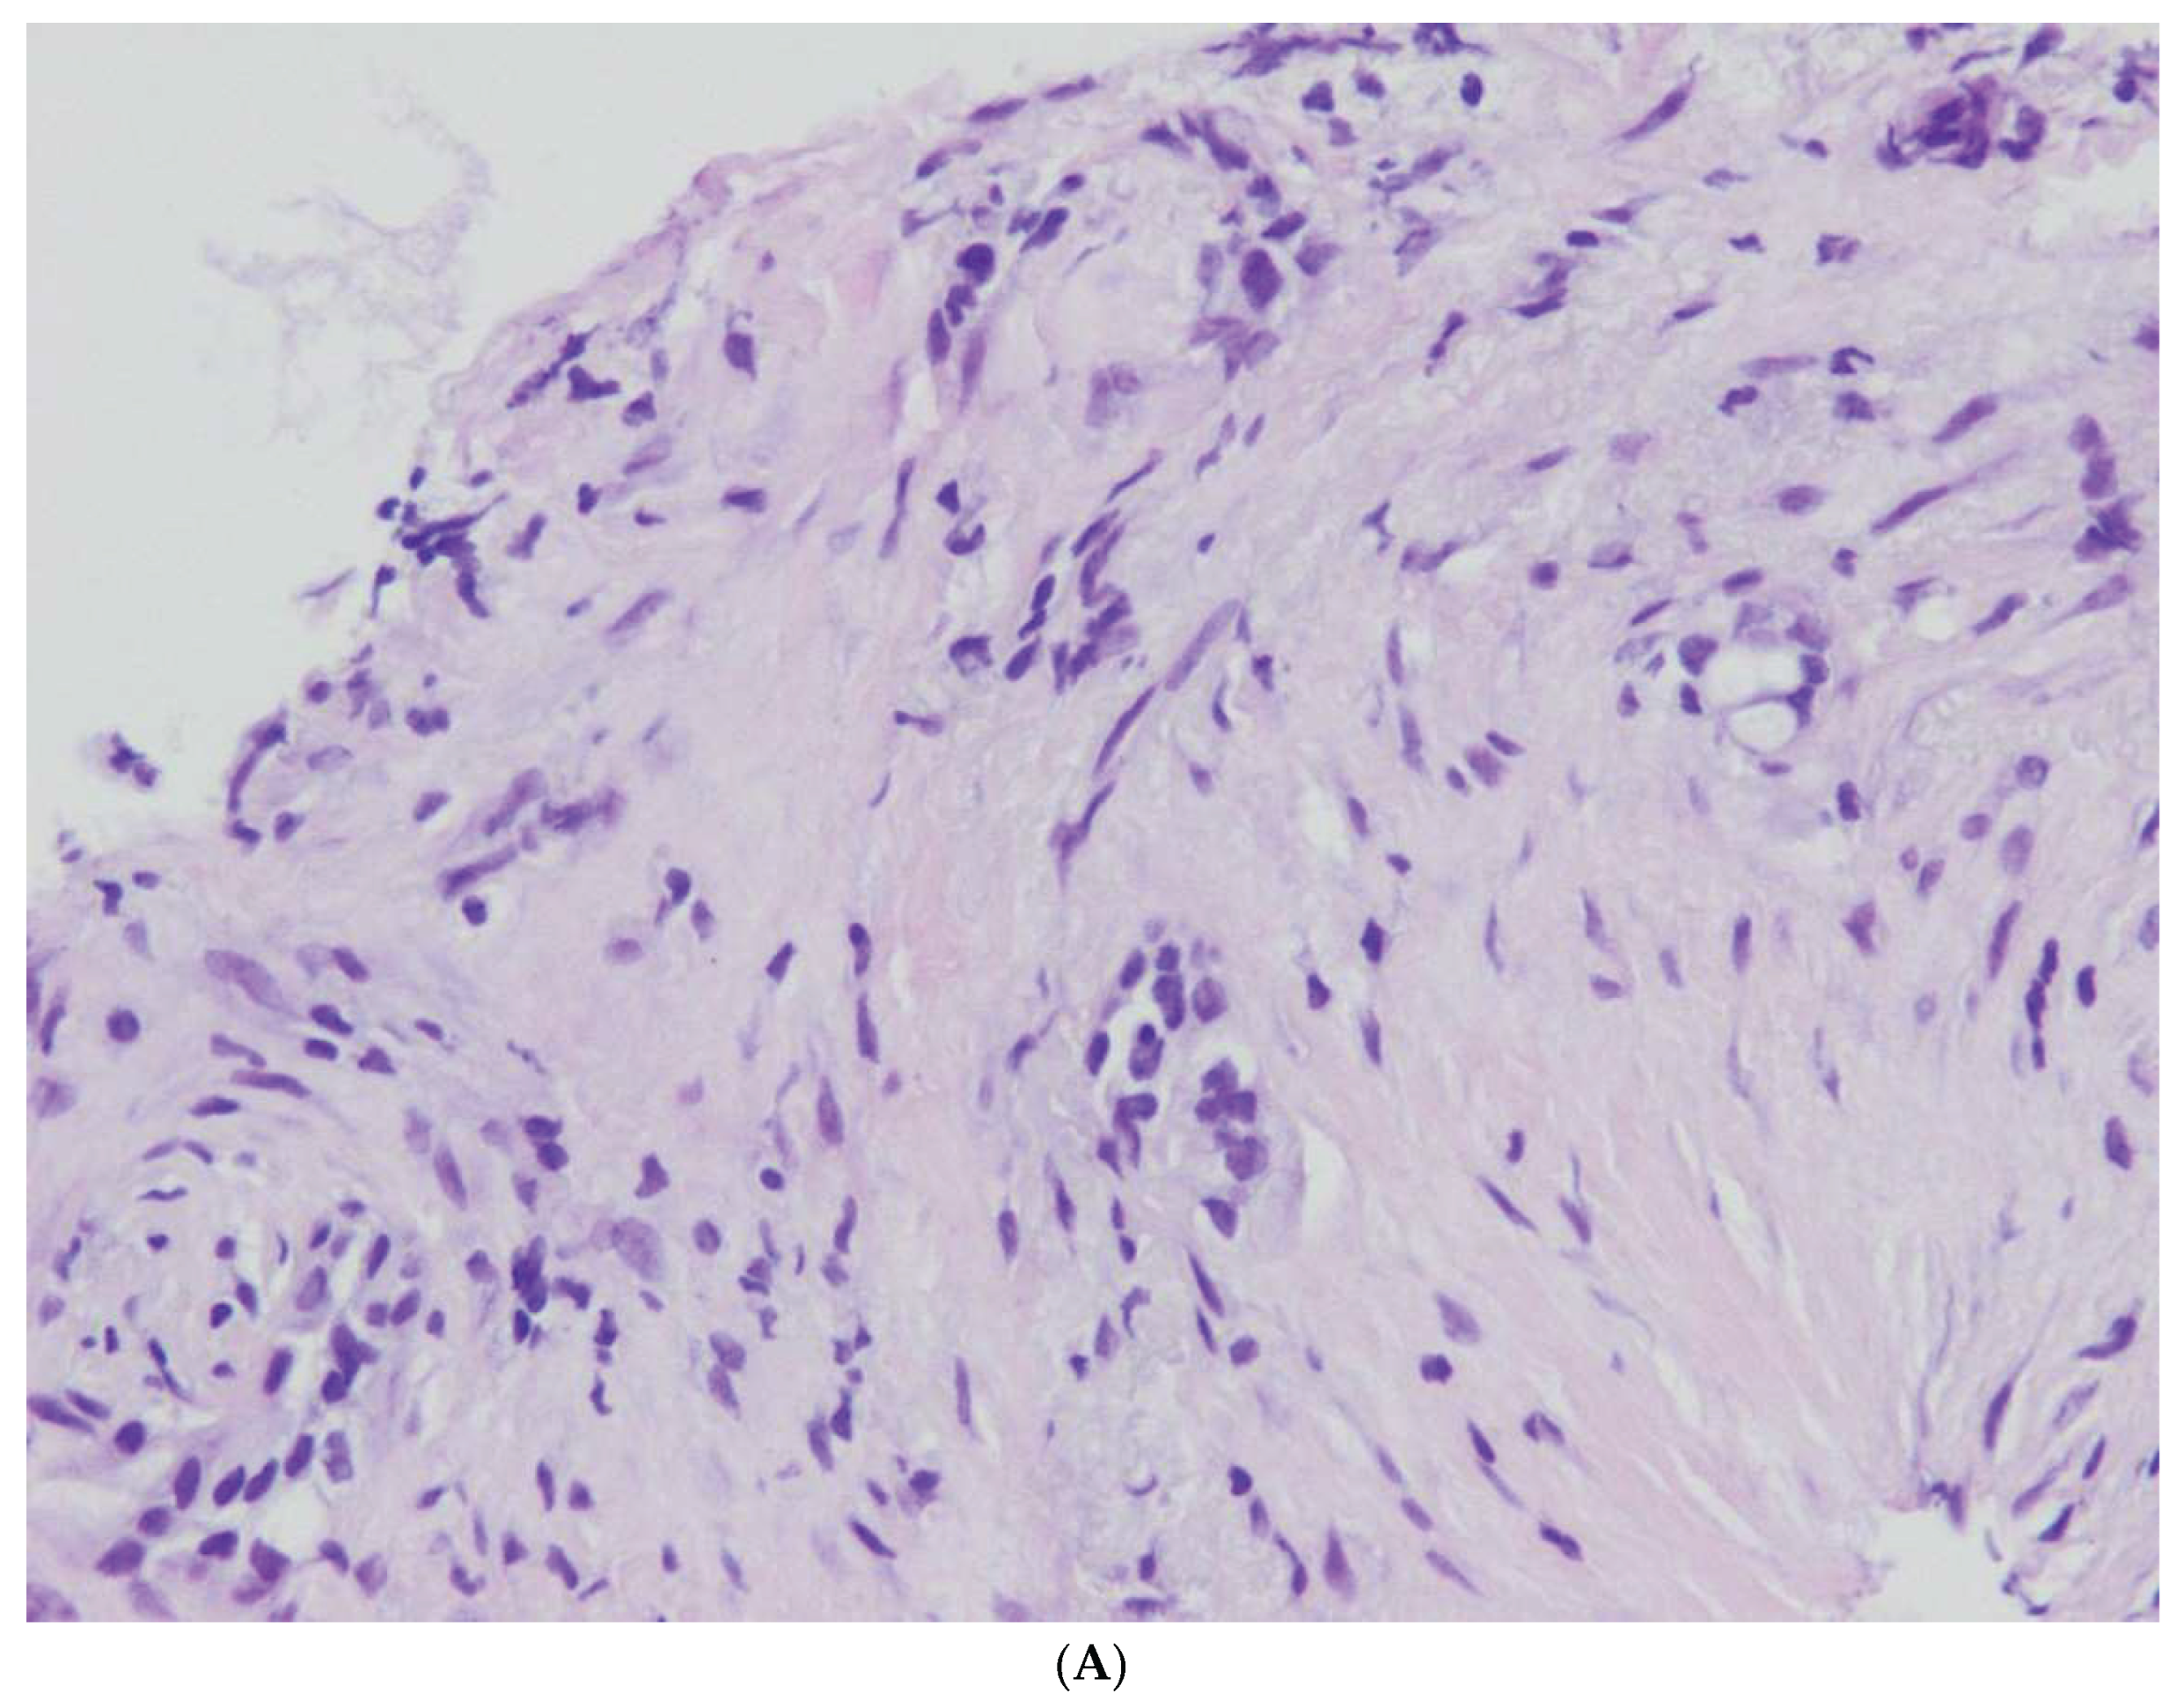

3.2.1. Pathomorphological Diagnosis of Specimen after da Vinci Robot-Assisted Surgery Method

3.2.2. Pancreatic Cancer Precursors